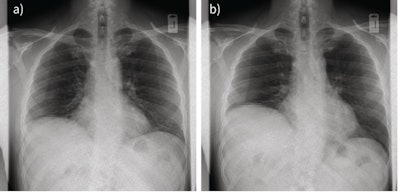

Dynamic chest radiography is a promising new tool for diagnosing patients with breathing symptoms related to diaphragm dysfunction, according to a study published on 21 February in European Respiratory Journal (ERJ) Open Research.

In a pilot study, U.K. investigators explored the use of dynamic chest radiography in a series of patients with symptoms suggesting diaphragm dysfunction. The technique provided promising real-time metrics on diaphragm and chest wall motion and warrants further study to see if it can complement established tools, such as ultrasound and traditional fluoroscopy, the authors suggested.

Dynamic chest radiography is a novel real-time digital fluoroscopic imaging system that produces clear, wide field-of-view diagnostic images of the thorax and diaphragm in motion, alongside novel metrics on moving structures within the thoracic cavity.

The researchers observed paradoxical motion (in which the diaphragm moves in the opposite direction than it should during inhaling and exhaling) in 14 patients, and they confirmed it in six who also underwent fluoroscopy or ultrasound. In four patients, dynamic chest radiography showed reduced hemidiaphragm excursion, but no paradoxical motion. In three patients, the researchers observed normal diaphragm motion.